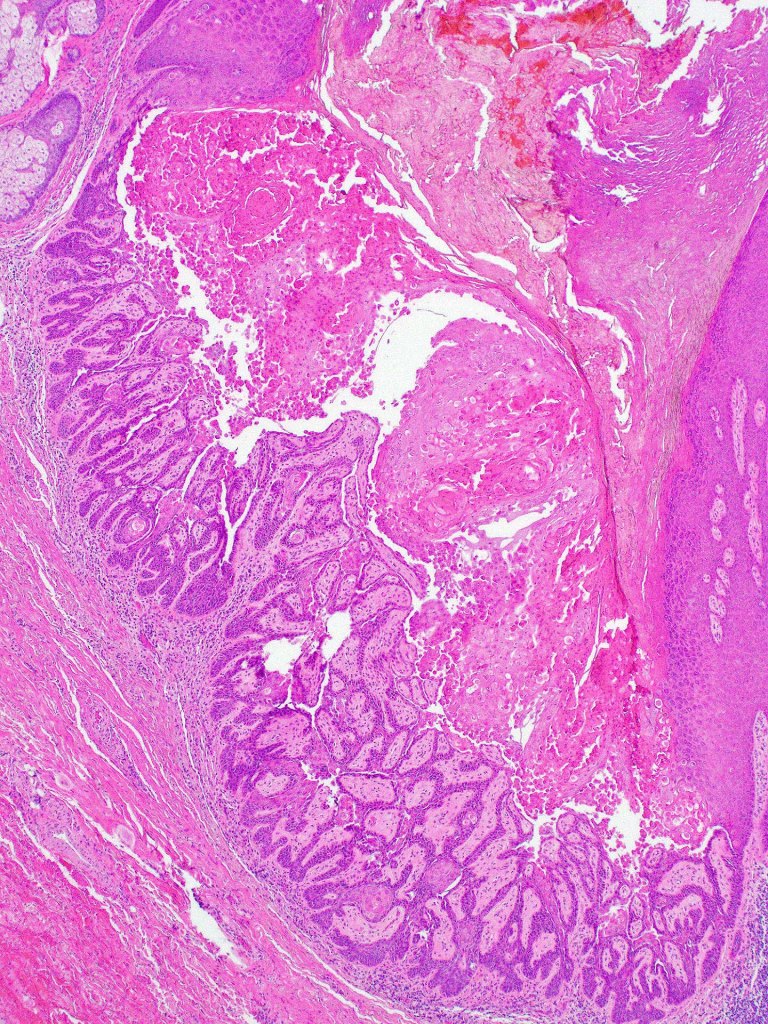

Warty dyskeratoma

•Umbilicated solitary nodule on sun-damaged skin of the head & neck but may arise elsewhere

•Rarely multiple lesions are present

•Follicular continuity often evident

•Cup-shaped, cystic invagination containing keratinous debris showing conspicuous corps ronds & grains of Darier

•The deeper reaches show acantholysis and prominent suprabasal villi